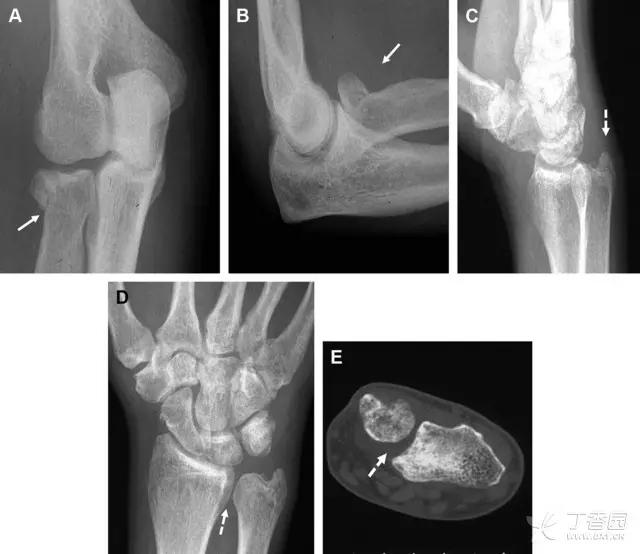

9. Essex-Lopresti 骨折

是桡骨头骨折伴有下尺桡关节脱位,导致骨间膜损伤,桡骨短缩。此种损伤,桡骨头骨折的诊断往往是明确的,容易忽视的是下尺桡关节脱位,特别是早期,下尺桡关节的症状不明显,X 线表示也不明显。

Essex-Lopresti 损伤。前后位(A)和侧位(B)示桡骨头关节内骨折(白色实线箭头);(C~E)伤后 1 个月复诊,患者诉腕关节疼痛,X 线(C,D)发现下尺桡关节脱位,(E)CT 进一步证实损伤的存在 (来源:Radiol Clin North Am. 2015 Jul;53(4):717-36)